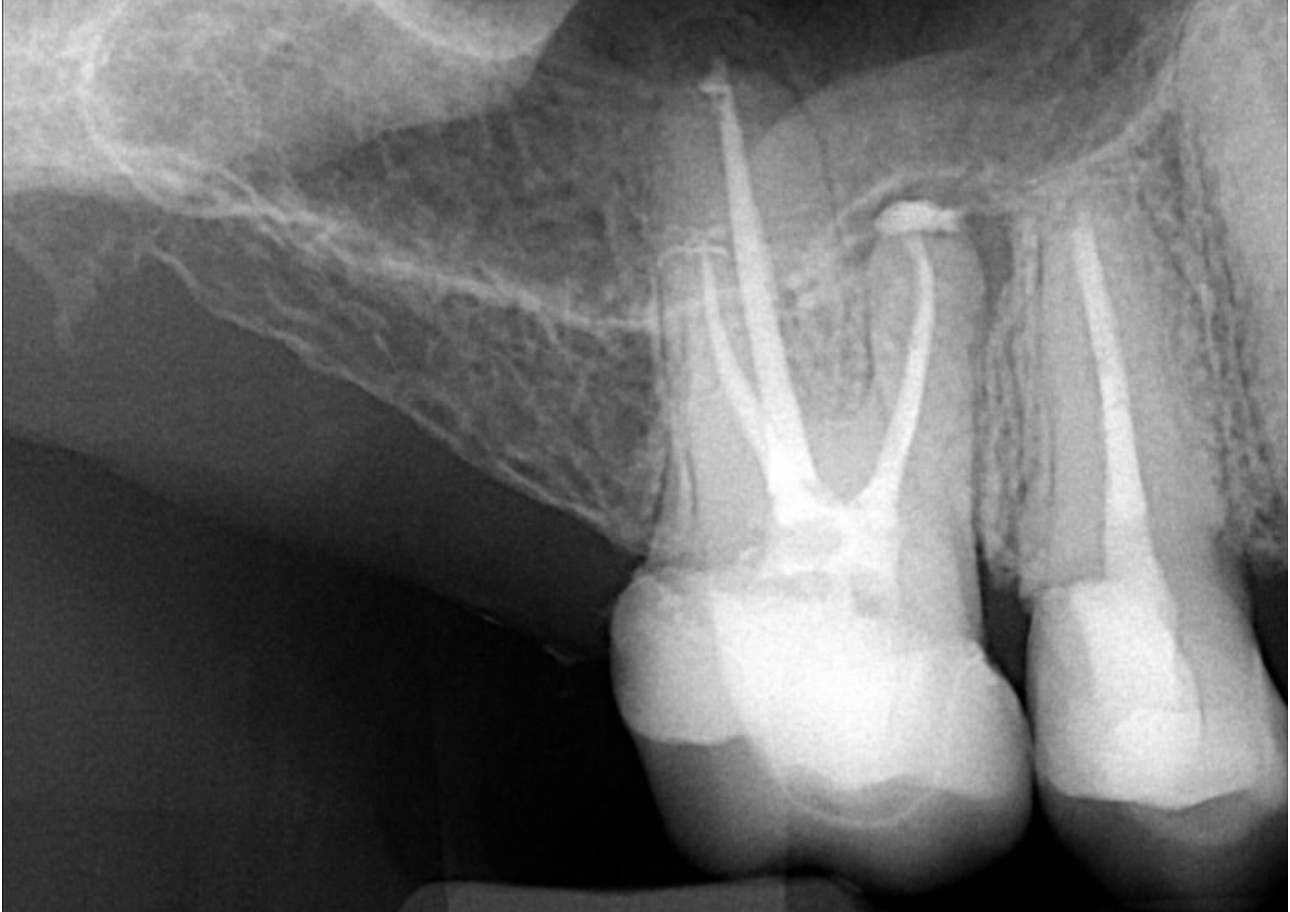

2. What option can be selected for the X ray bellow?